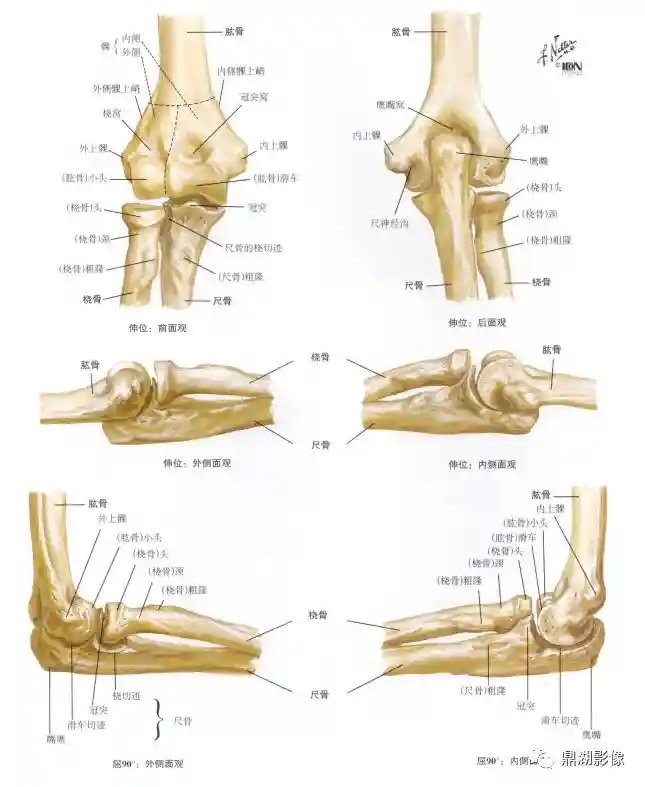

肱骨

肱骨分一体两端

上端朝向后内方呈半球形为肱骨头,头周围的环状浅沟为解剖颈,上端与体交界处稍细为外科颈

体上半部呈圆柱形,下半部呈三棱柱形,后面中部有桡神经沟(桡神经和肱深动脉)

下端较扁,内上髁后方有尺神经沟(尺神经)

桡骨、尺骨

桡骨:居前臂外侧,分一体两端,上端膨大为桡骨头,头下略细为桡骨颈,下端前凹后凸,外侧向下突出为茎突

尺骨:居前壁内侧,分一体两端;上端粗大,前面有一类圆形深凹为滑车切迹,其后上方突起为鹰嘴;下端为尺骨头